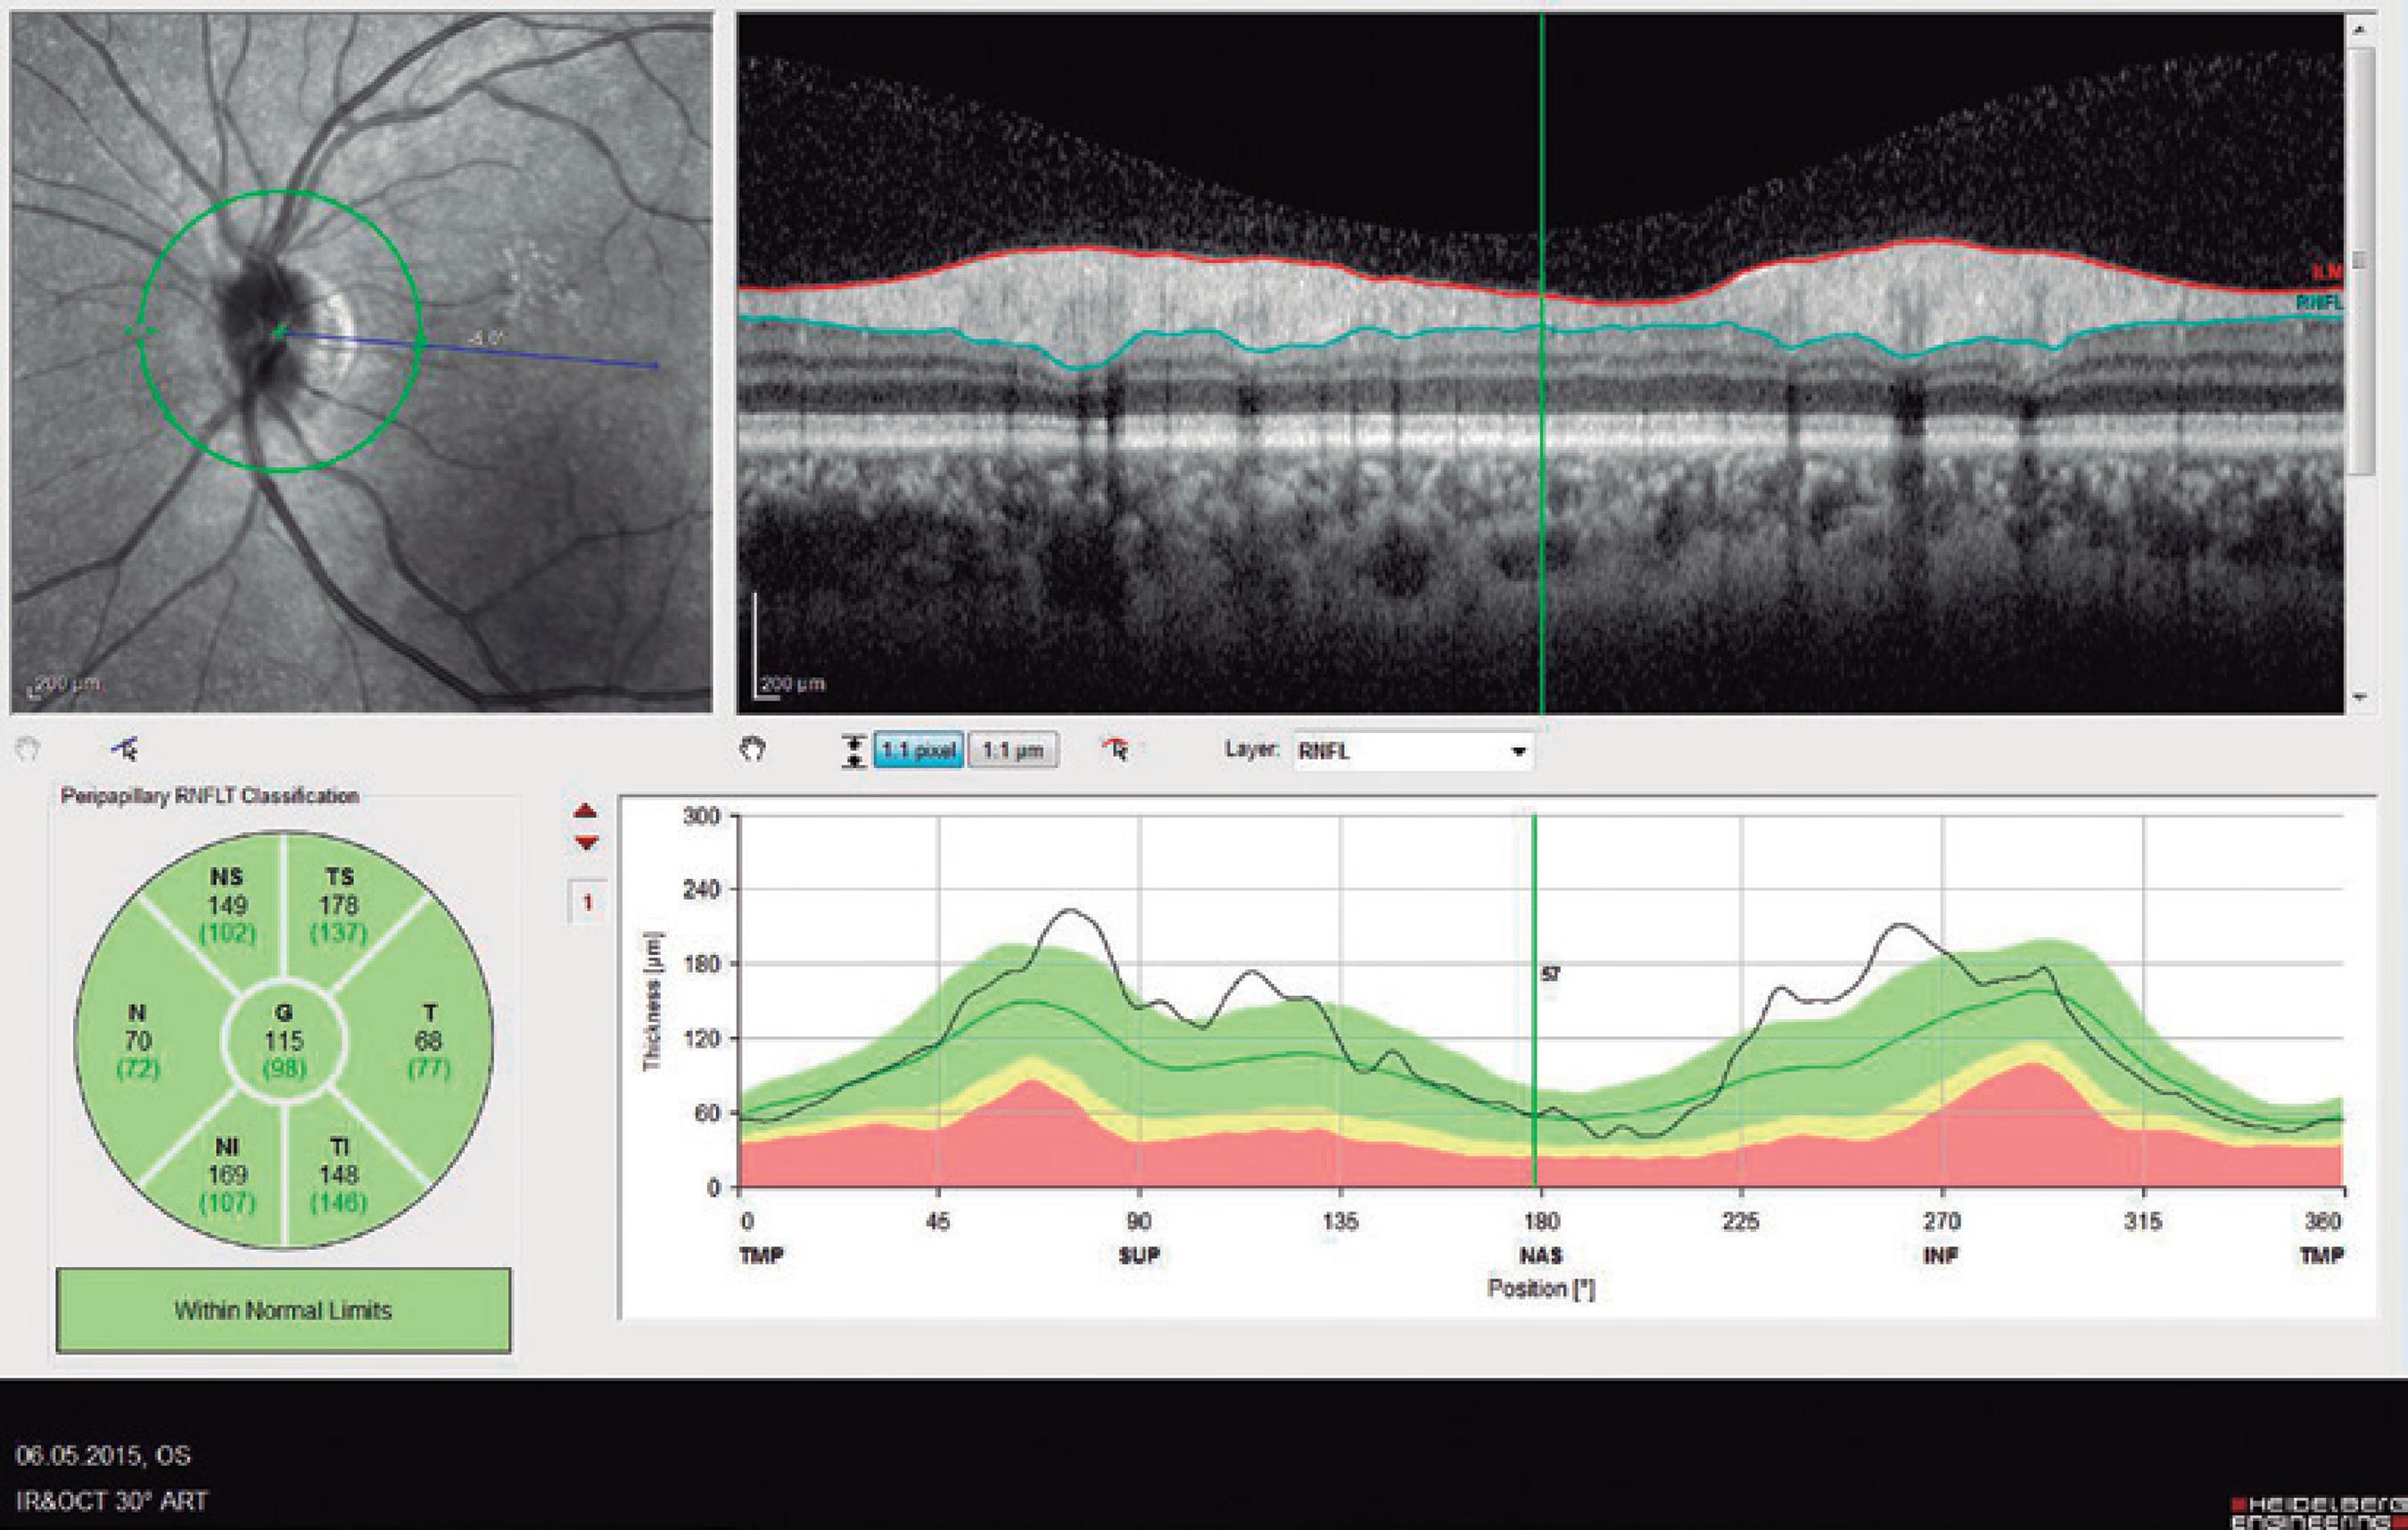

Ninety eyes of 45 healthy subjects and 104 eyes of 52 patients with BD were included in the study. Of the 52 patients with BD, 25 had ocular involvement and 27 did not. The patients without ocular involvement had no history of previous ocular Behçet. This study was approved by the local ethics committee, and the study protocol adhered to the tenets of the Declaration of Helsinki. Informed consent was obtained from each patient in both groups. The patients underwent complete ophthalmic examination, including biomicroscopy and fundoscopy. Additionally, OCT measurements were obtained using an SD-OCT device (Spectralis OCT, Version 6.0; Heidelberg Engineering, Germany) with an enhanced depth-imaging mode without pupil dilation. A standardized examination of all subjects was performed. All measurements were performed by the same experienced examiner (ASK) in the morning. RNFL, GCL, IPL, and CT were measured and recorded. The new Spectralis segmentation software was used to obtain RNFL, GCL, and IPL. The SD-OCT choroid layer, RNFL, GCL, and IPL imaging of a normal eye are shown in figures 1,2, 3, and 4, respectively.

Figure 2 Spectral domain optical coherence tomography retinal nerve fiber layer (RNFL) imaging of a normal eye.